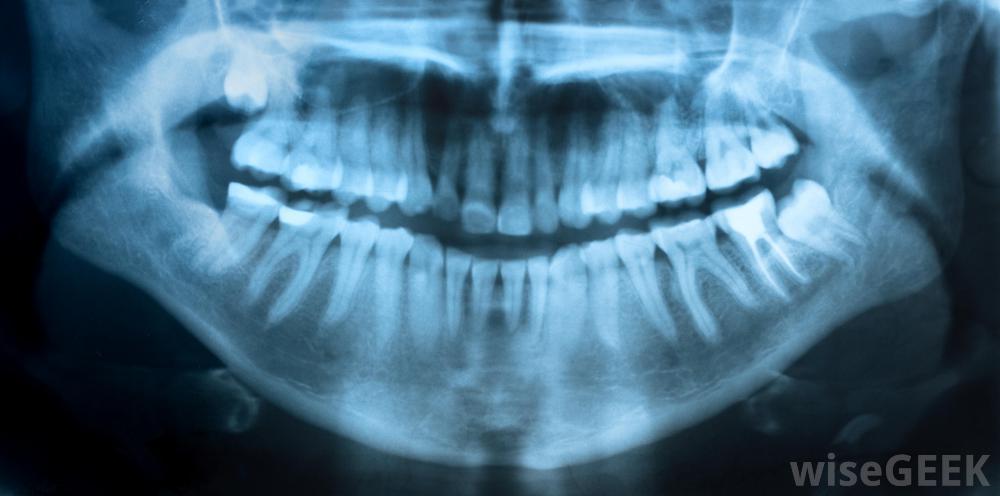

流動牙醫經常攜帶進行牙科x光檢查所需的設備。

由于高質量的牙科護理需要使用一系列設備、牙科制劑和藥物,因此移動牙科服務通常乘坐一輛面包車或卡車,配備齊全所需的工具護理。雖然此類車輛中的設備通常取決于服務計劃提供的護理類型,但這些貨車和卡車通常包括進行牙科檢查、填充空洞、涂抹牙科密封劑、清潔患者牙齒所需的x光設備和工具,一些移動牙科車甚至配備了拔牙設備。